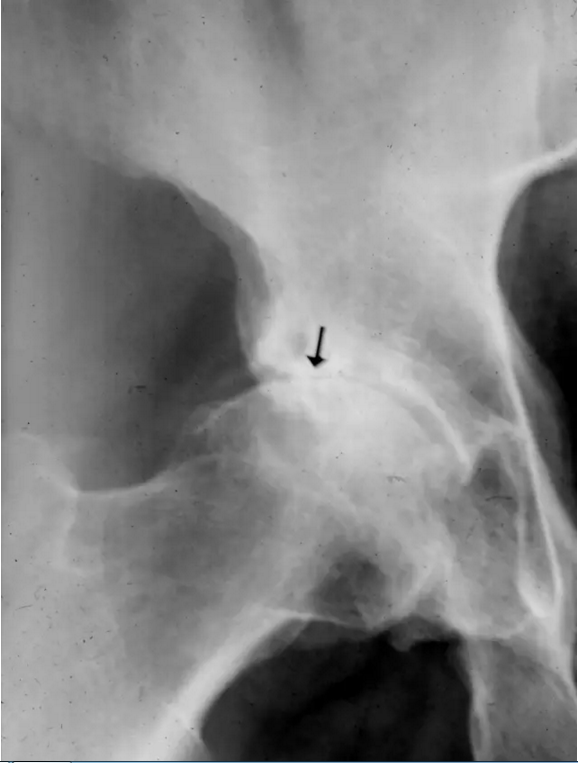

患者的臀部的蛙式位图片,新月征显示缺血坏死志,表明软骨下骨折。 一旦出现这种迹象,治疗性干预就不太可能阻止疾病的进展。新月征是指股骨头负重区软骨下骨板内1~2mm厚的透光区,是由于骨坏死后,骨质被吸收,出现微骨折所致,通常在正位片上不易见到,在蛙式位片上易显示,容易被忽视。

该患者的缺血坏死显示新月标志,表明软骨下骨折。 一旦出现这种迹象,治疗性干预就不太可能阻止疾病的进展。